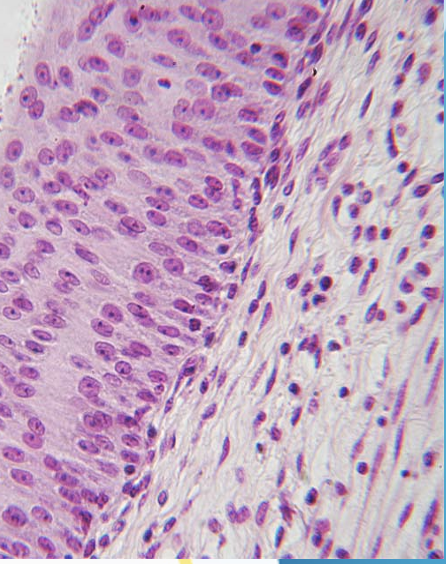

Stratified Squamous Epithelium

(Lining the esophagus)

<p>(Lining the esophagus)</p>

Line the esophagus, mouth, and vagina